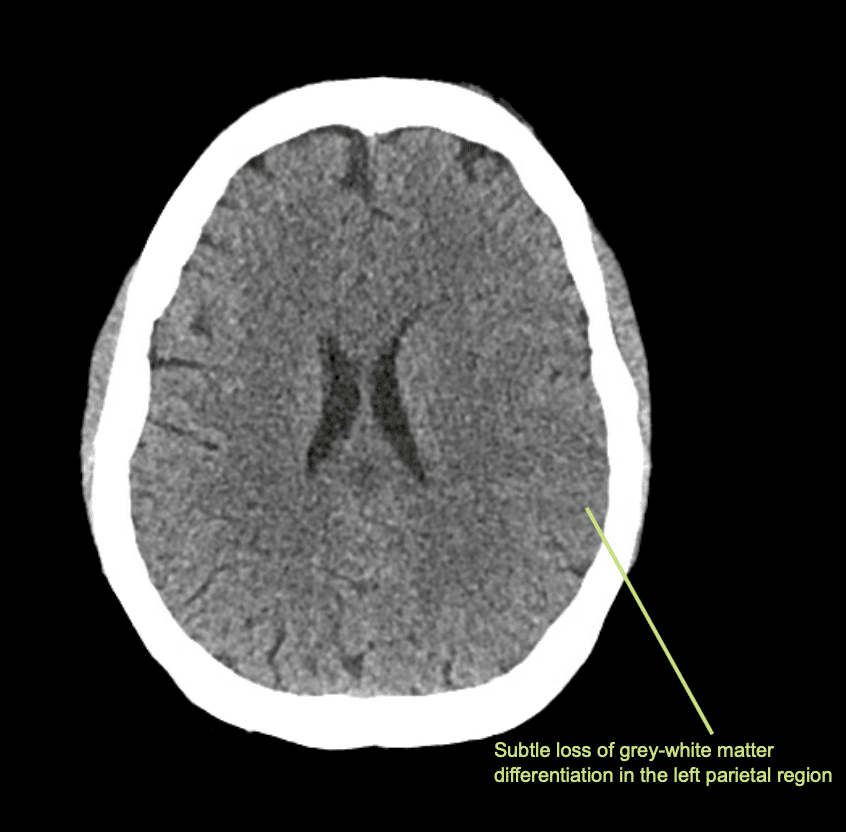

Descrivi e interpreta la TAC

Interpretazione della TAC